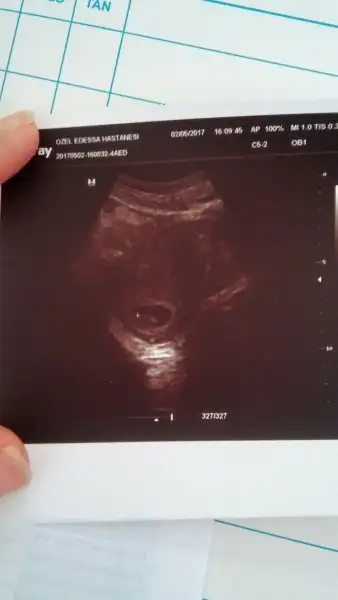

Eki Görüntüle 2001512 Herkes yukleyince ben de eksik kalmayayim dedim 9+5 haftalik resmimiz yarin tekrar gidecegiz

Birincii resim 7 haftalik.

Kızlar çıktım çok şükür herşey süper dedi doktorum ilk kontrolde ekranda kalp sesini görmüştüm şimdi duydum Allahım herkese yaşatsın nefesim kesildi sandım9+5 deyiz ve 3 cm olmuş sıpam :)

daha güzel günlerını de goresın bebişininKızlar çıktım çok şükür herşey süper dedi doktorum ilk kontrolde ekranda kalp sesini görmüştüm şimdi duydum Allahım herkese yaşatsın nefesim kesildi sandım9+5 deyiz ve 3 cm olmuş sıpam :)

Çoookk sevindim canım benim..Sonun kadar hep güzel haberler almayı nasip etsin Rabbim..Şimdi bu mutluluğun tadını çıkar bol bolKızlar çıktım çok şükür herşey süper dedi doktorum ilk kontrolde ekranda kalp sesini görmüştüm şimdi duydum Allahım herkese yaşatsın nefesim kesildi sandım9+5 deyiz ve 3 cm olmuş sıpam :)

Cok sevindim canim maasallah.Kızlar çıktım çok şükür herşey süper dedi doktorum ilk kontrolde ekranda kalp sesini görmüştüm şimdi duydum Allahım herkese yaşatsın nefesim kesildi sandım9+5 deyiz ve 3 cm olmuş sıpam :)